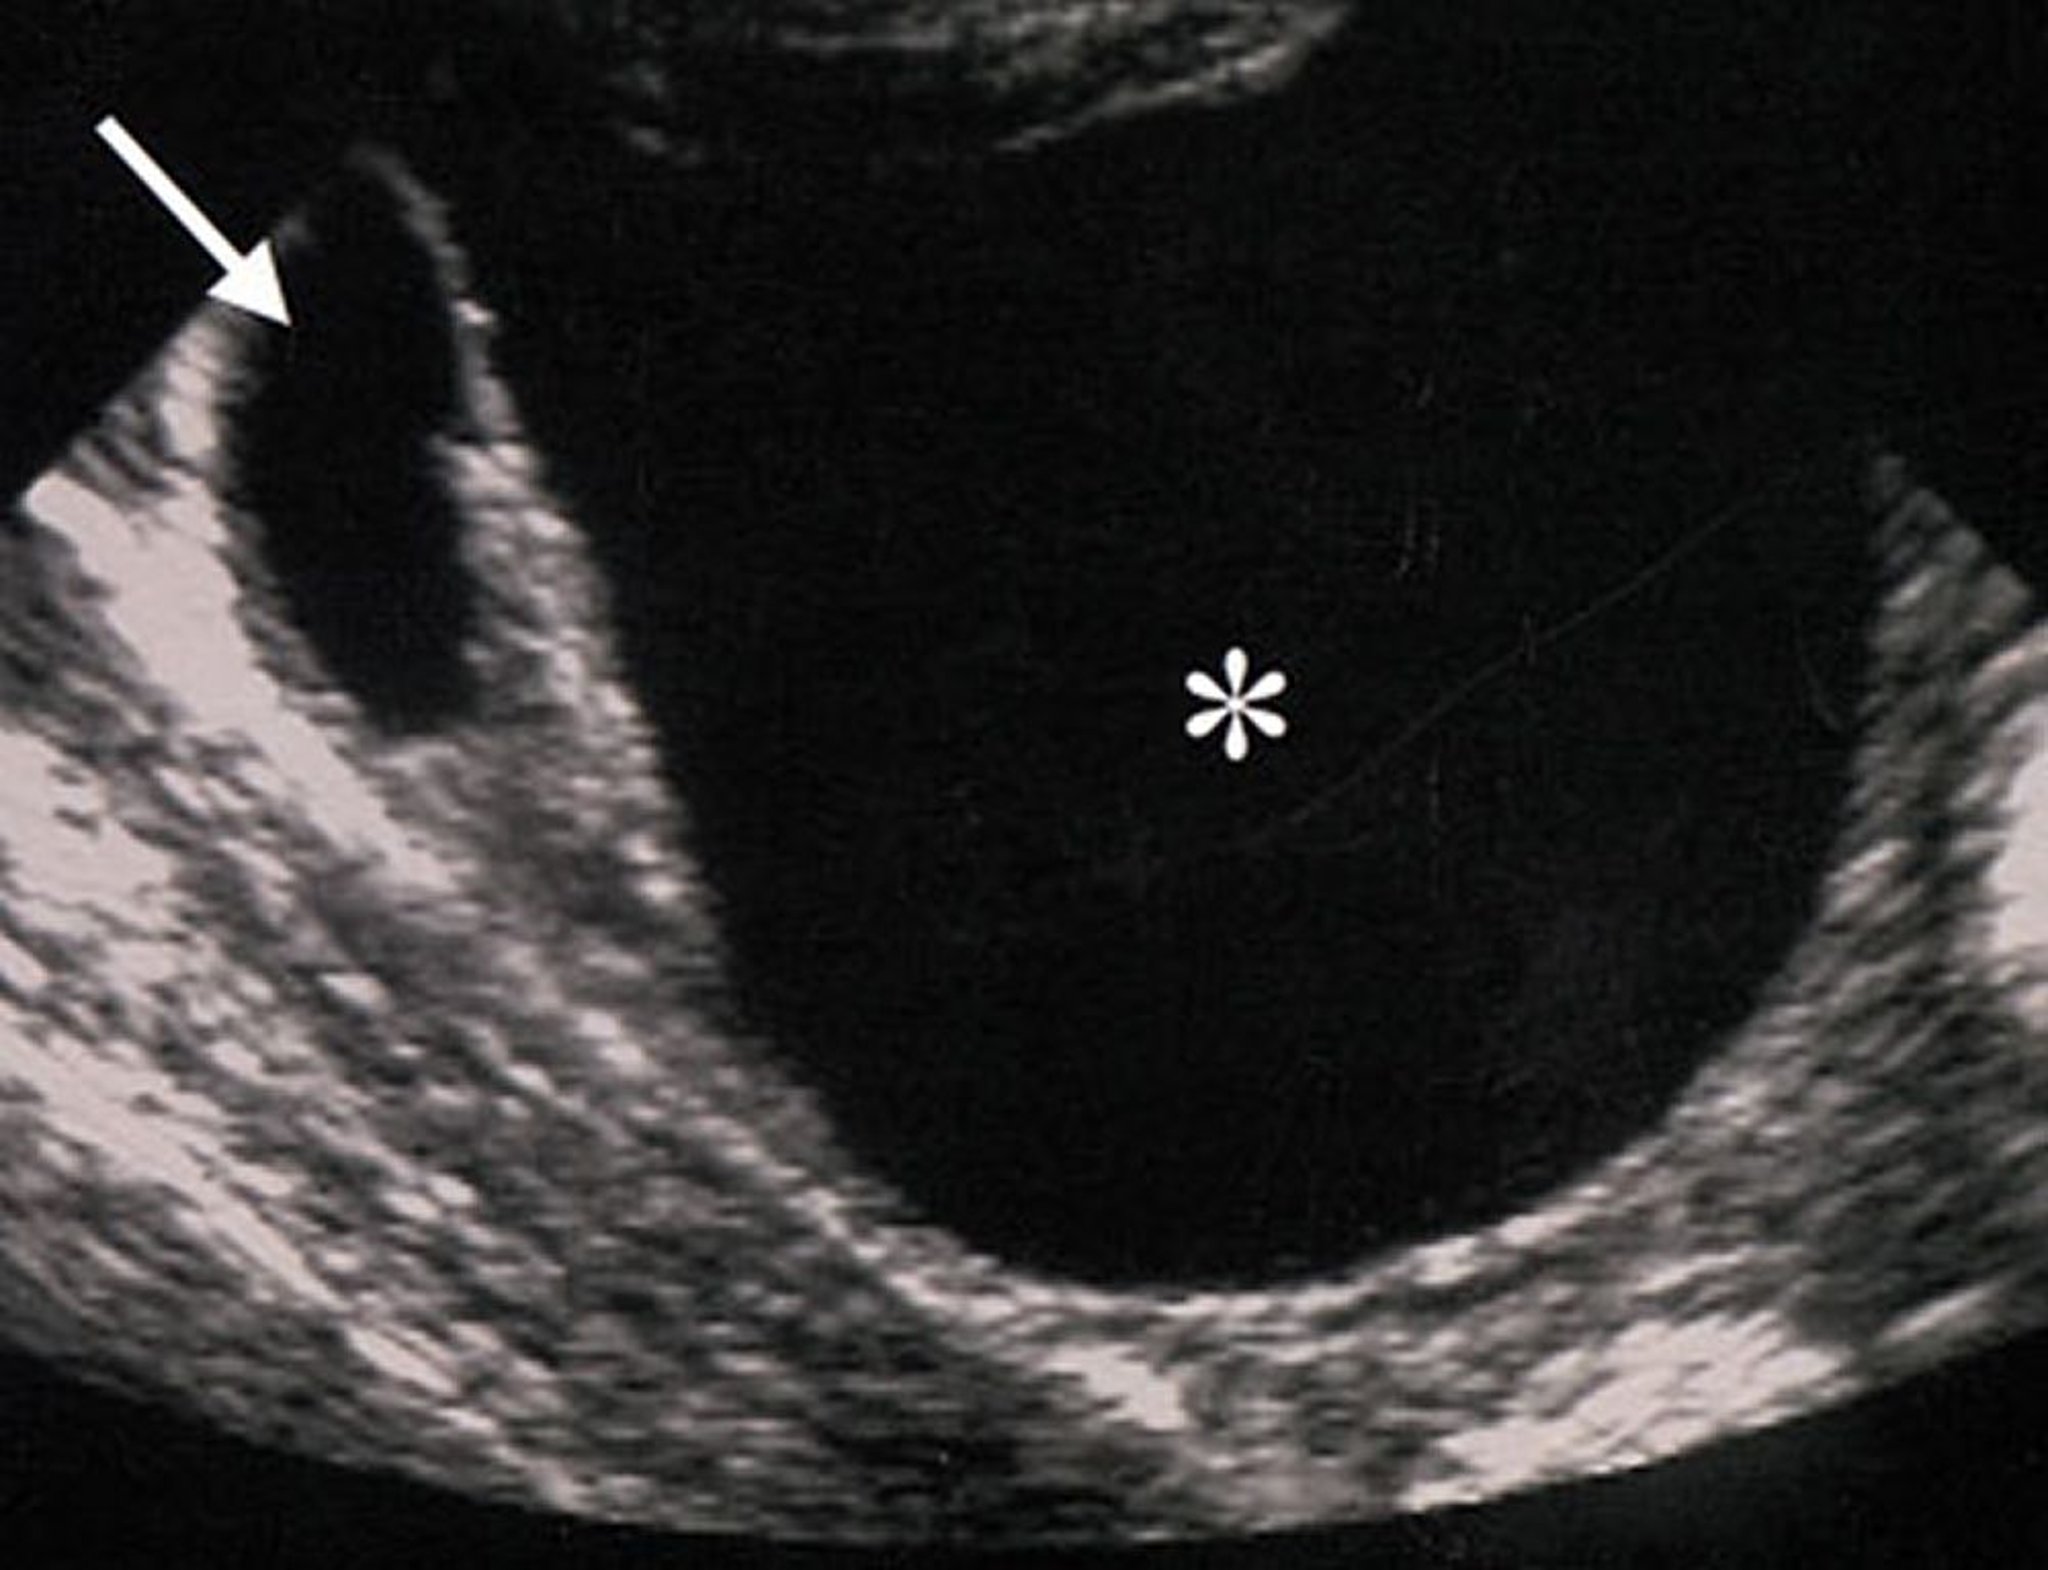

Ultraschall einer gutartigen ovariellen Raumforderung

Die Ultraschallmerkmale dieser ovariellen Raumforderung (mit einem Sternchen gekennzeichnet) deuten darauf hin, dass die Raumforderung gutartig ist. Die Raumforderung ist echofrei (was darauf hindeutet, dass keine festen Bestandteile vorhanden sind), regelmäßig, gut umschrieben und ohne Wandverdickungen oder Auswüchse.